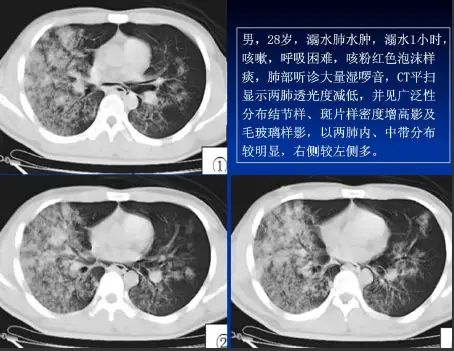

病例:男,28岁,溺水肺水肿,溺水1小时,咳嗽,呼吸困难,咳粉红色泡沫样痰,肺部听诊大量湿啰音。

CT表现

肺泡性肺水肿:两肺透光度减低,并见广泛性分布结节样、斑片样密度增高影及毛玻璃样影,以两肺内、中带分布较明显,右侧较左侧多。

溺水性肺水肿,以肺泡性为主,右肺明显,结合病史即可明确诊断。